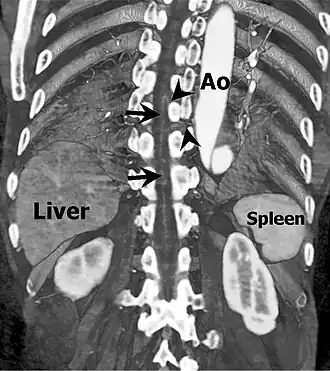

Coronal slab volume rendering image of CT aortography shows artery of Adamkiewicz entering spinal canal(arrowheads) and joining the anterior spinal artery (arrows) after a hairpin turn. | |

The artery has a characteristic "hairpin" turn on the cord surface as it first courses superiorly, then turns inferiorly. In 75% of people, it originates on the left side of the aorta between the T8 and L1 vertebral segments.[11] In addition to being able to be either right or left-sided, the vessel can arise from a lumbar artery instead of from the aorta.[5]